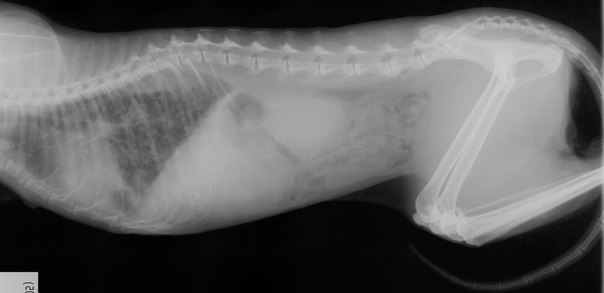

| Рентгенография | Позволяет визуализировать жидкость в брюшине, проверить состояние органов и наличие новообразований. Однако при большом объеме транссудата метод оказывается неэффективным |

Для визуализации жидкости в брюшной полости используют такие методы диагностики, как рентгенография и ультразвуковое исследование.

На рентгенологическом снимке при небольшом количестве асцитной жидкости оценивают размеры печени, почек, лёгких, сердца, обращают внимание на наличие или отсутствие новообразований. Если же количество жидкости велико, то рисунок органов брюшной полости становится нечётким.

Рентген брюшной и грудной полости при массивном асците у кошек подтверждает наличие жидкости, при умеренном или среднем позволяет оценить состояние органов и исключить новообразования. Эхокардиографию сердца проводят для оценки состояния и функциональной полноценности органа.